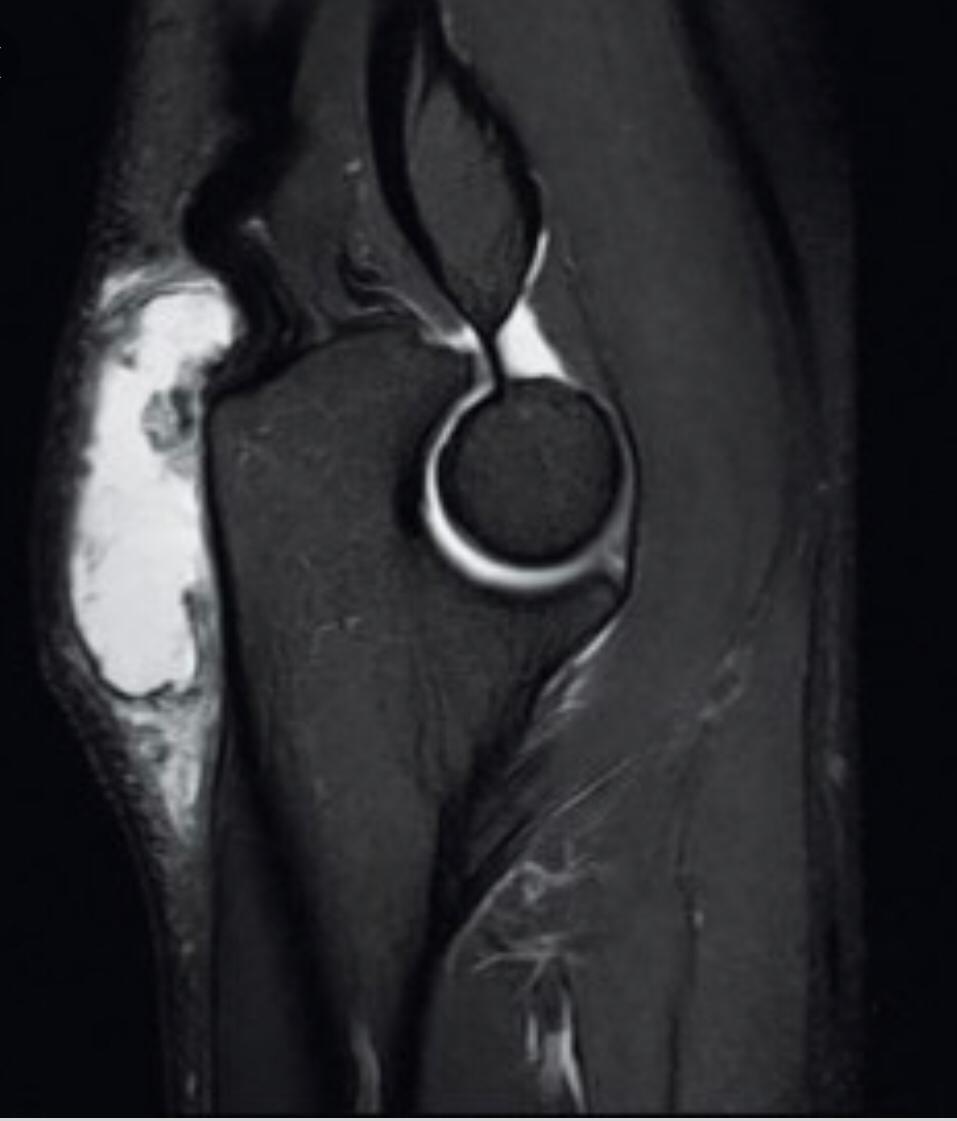

MRI is a study of choice for any abnormal findings on post-reduction radiographs such as joint widening. In MR study, in inspect for joint incongruity or nonconcentric reduction. Entrapped labrum or capsule is best evaluated via MRI.

CT is second choice behind MRI for post-reduction evaluation, and also radiation exposure should be considered. Osteochondral fragments can be seen in older children and are easily detected by CT.